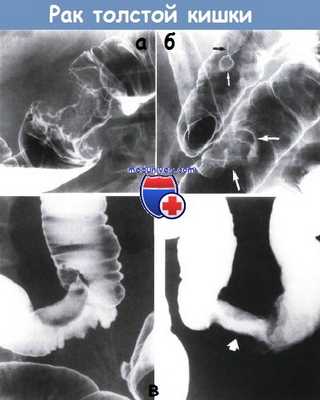

а - Кольцевидный рак середины поперечно-ободочной кишки. Видно круговое сужение длиной 4 см с выступающими краями и узловатой слизистой оболочкой.

Клизма с барием, двойное контрастирование.

б - Сосуществующие аденокарцинома и тубулярная аденома. В области ректосигмо-идного соединения обнаружен полиповидный рак (показано большими белыми стрелками, контур белого цвета).

В проксимальной части сигмовидной кишки видна ножка (черная стрелка) и верхушка (маленькая белая стрелка) тубулярной аденомы. Клизма с барием, двойное контрастирование

в - Переходная форма между полипом и кольцевидной карциномой — «полукольцевой» или «седловидный» тип поражения.

На одном из снимков видно полиповидное образование в проксимальной части сигмовидной кишки. Противоположная от полиповидного образования стенка кишки (показана белыми стрелками) втянута в область частичной круговой инфильтрации опухоли.

На снимке в прямой проекции заметно новообразование (показано стрелкой), охватывающее толстую кишку по окружности. Клизма с барием, двойное контрастирование.